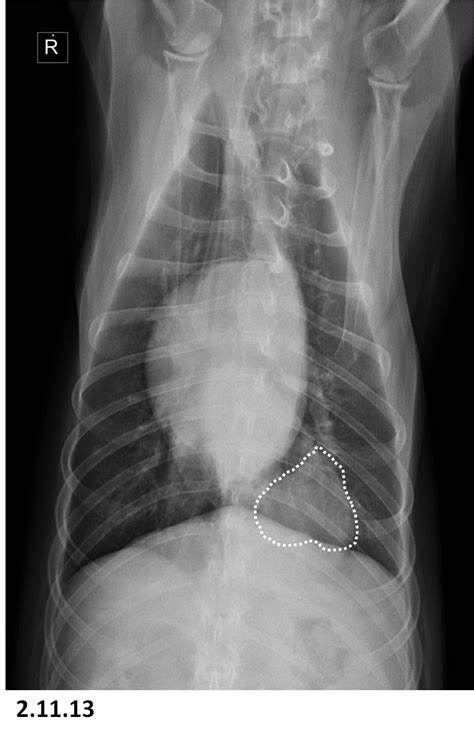

prednisone and lung cancer - DylanBrackett1's blog from dogsontherun.net Tuberculous pneumonia, although uncommon, is sometimes seen in dogs. Antibiotics for pneumonia in adults in hospital, nice, 09.10.2020. Pneumonia occurs when the lungs and airways become inflamed due to a response to injury, irritation, or infection. Pneumonia is an inflammation of the lungs and airways that causes breathing difficulties and deficiency of oxygen in the blood. She made her way to vet ranch and made an incredible turn around! Agility and collaboration toward a common goal. General cancer symptoms in dogs. Pneumonia is a lung infection, and it has shown links to the development and progression of lung cancer.

Canine pneumonia can be as dangerous for dogs as it can be for humans, with potential fatality if left without treatment. Over the lungs in consolidation of the pulmonary tissue (acute lobar pneumonia, tuberculosis, lung infarction, compressive atelectasis), cavity in the lungs (abscess, caverna). Causes of pneumonia in dogs. Pneumonia occurs when the lungs and airways become inflamed due to a response to injury, irritation, or infection. Dog pneumonia can sometimes cause a dog cough. She made her way to vet ranch and made an incredible turn around! Parasitic invasion of the bronchi can also result in pneumonia. Pneumonia and lung cancer both affect the lungs, but while the former is easily treatable and the latter is oftentimes life threatening. Lung cancer and pneumonia have similar symptoms, and both can be fatal. Antibiotics for pneumonia in adults in hospital, nice, 09.10.2020. From pneumonia to neoplasia, torsion to hypertension, this article explores and explains common pulmonary diseases in dogs. Pneumonia is an inflammation of the air sacs of the lungs. A nationwide analysis in china.

Over the lungs in consolidation of the pulmonary tissue (acute lobar pneumonia, tuberculosis, lung infarction, compressive atelectasis), cavity in the lungs (abscess, caverna). Lung cancer usually occurs in older patients, is not breed specific and can be due to environmental factors. Types of lung carcinoma in dogs. Initial stage of lobar pneumonia b. After a physical exam and using a stethoscope to.

Over the lungs in consolidation of the pulmonary tissue (acute lobar pneumonia, tuberculosis, lung infarction, compressive atelectasis), cavity in the lungs (abscess, caverna). Lung cancer in dogs is serious, but it is treatable. What are the overlapping symptoms and outlook? Dogs can get the same types of cancer as people. If a person has lung cancer and gets pneumonia, the prognosis and life expectancy is poor. Initial stage of lobar pneumonia b. How do dogs get pneumonia? Pneumonia occurs when the lungs and airways become inflamed due to a response to injury, irritation, or infection. Dog pneumonia can sometimes cause a dog cough. Lung cancer (adenocarcinoma) in dogs. Types of lung carcinoma in dogs. Two common reasons this could happen is if. Anaerobic bacterial infections of the lung and pleural space.